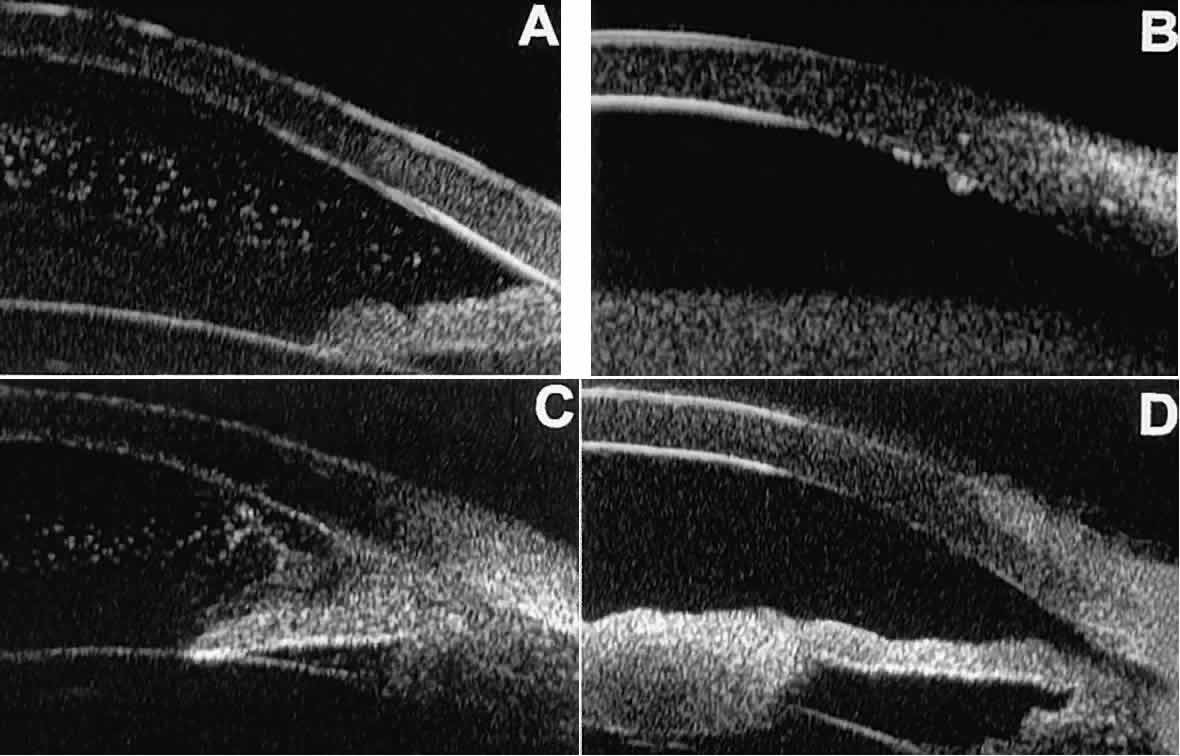

In most patients, the anterior segment can be evaluated thoroughly by slit lamp biomicroscopy unless the cornea is cloudy or opaque. In eyes with a cloudy or opaque cornea, UBM can be used to evaluate the cornea and to define the nature of underlying abnormalities in the angle, iris, ciliary body, lens, and anterior vitreous.4 For example, in eyes with severe congenital malformations of the anterior segment associated with a cloudy or opaque cornea (e.g., Peter's anomaly) (Fig. 14), UBM can be used to define the full extent of the abnormalities and thereby aid the clinician in deciding whether or not to consider any surgical intervention. UBM can also be used to study the extent of some clinically evident corneal abnormalities, such as corneal edema, bullous keratopathy, and band keratopathy (Fig. 15). In eyes with corneal edema (see Fig. 15A), UBM shows the epithelium to be thicker than normal and the stroma to have increased reflectivity. In bullous keratopathy (see Fig. 15B), UBM shows epithelial blisters of the cornea. In band keratopathy (see Fig. 15C), UBM shows superficial calcific deposits that are strongly reflective with shadowing of the underlying structures. In postinflammatory corneal scarring (see Fig. 15D), UBM can show the nonuniform cross-sectional corneal thickness and the presence or absence of a well-defined Descemet's membrane and endothelium layer.

Fig. 14. UBM features of eyes with Peter's anomaly. A. Mild posterior central corneal excavation, absence of Descemet's membrane and endothelium centrally, iridocorneal adhesions to margins of corneal defect, and diffuse hyper-reflectivity of corneal stroma. B. Different patient showing detail of posterior central corneal excavation and diffuse hyper-reflectivity of corneal stroma.

Fig. 15. UBM features of miscellaneous corneal disorders. A. Corneal edema appears as thickening of superficial layer of cornea; corneal stroma is thinner than normal and abnormally bright. B. Bullous keratopathy appears as localized separation of corneal epithelium from Bowman's membrane filled with clear serous fluid. C. Band keratopathy appears as dense, brightly reflective subepithelial plaque in peripheral cornea. D. Postinflammatory corneal scarring after keratitis; note nonuniform corneal thickness and abnormal reflectivity of corneal stroma.

Ultrasound biomicroscopy has also been used to evaluate several anterior scleral disorders,11 including nodular anterior scleritis and scleral hyaline plaques (Fig. 16). On UBM, nodular anterior scleritis (see Fig. 16A) appears as a localized thickening and altered reflectivity of the inflamed sclera. In diffuse non-necrotizing anterior scleritis (see Fig. 16B), UBM shows generalized pronounced thickening of the sclera in the region of involvement. In contrast, after a bout of necrotizing anterior scleritis, UBM can show thinning of the damaged sclera (see Fig. 16C). In eyes with one or more scleral hyaline plaques (see Fig. 16D), UBM shows the lesion to be a highly sonoreflective plate located just anterior to the insertion of the medial or lateral rectus muscle; the lesion has well-defined margins and is so sonoreflective that it shadows the underlying layers of the eye wall.

Fig. 16. UBM features of anterior scleral disorders. A. Nodular anterior scleritis appears as fusiform thickening of limbal sclera. Note apparent lamellae of heterogeneous reflectivity within region of thickening. B. Diffuse anterior scleritis appears as nonfocal scleral thickening in region of inflammation. C. Scleral thinning subsequent to necrotizing anterior scleritis. Note underlying vitreous cells. D. Scleral hyaline plaque appears as dense, hyper-reflective plate several millimeters from horizontal limbus; dense lesion “shadows” deeper tissues.